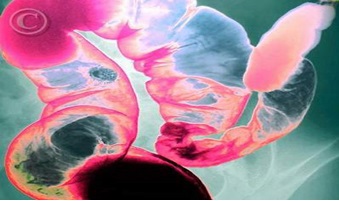

09:40 CH @ 03/05/2019Vừa qua Phòng khám Chuyên khoa Ký sinh trùng, Viện Ký sinh trùng và Côn trùng TP.HCM đã khám và điều trị cho một trường hợp điển hình bị bệnh rận mu, đó là bệnh nhi đến khám với tình trạng sưng tấy, đỏ kèm theo ngứa vùng quanh mắt. Qua thăm khám, bệnh nhi được chẩn đoán bị rận mu kí sinh quanh mi mắt.Nhân một trường hợp phát hiện bị ấu trùng mò (Chigger mite) đến khám tại Phòng Khám chuyên khoa Ký sinh trùng